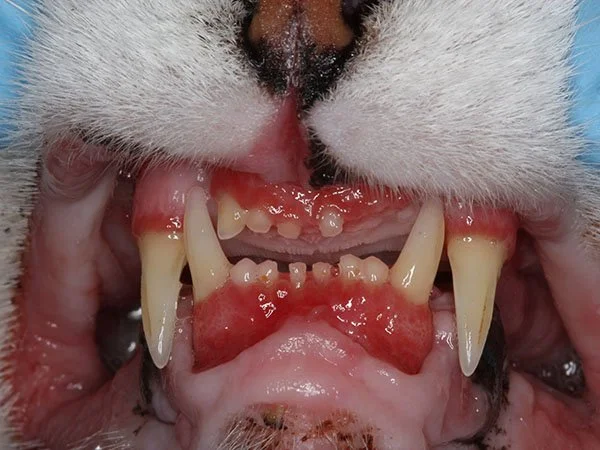

• Feline Chronic Gingivostomatitis (FCGS): This painful oral disease often requires full-mouth extractions. However, studies (Frontiers in Vet Science, 2023) show that stem cells can significantly reduce oral inflammation and promote healing in refractory cases by modulating the T-cell response, offering long-term relief from this disease process.